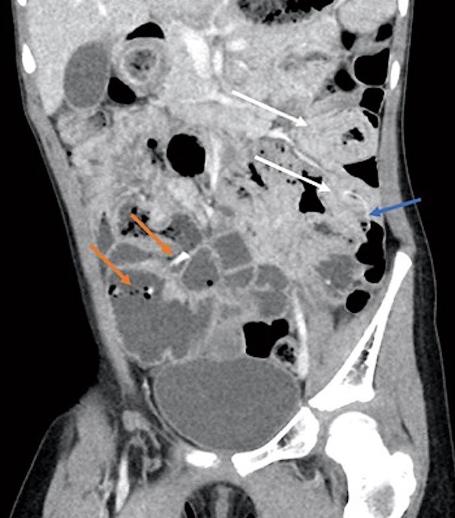

腹部和骨盆的CT与静脉造影显示多个突出的空气和充满液体的肠袢贯穿腹部。结果涉及回肠-回肠、回肠-结肠和结肠-结肠肠套叠累及远端横结肠/近端降结肠(图3、4、3、4)。在影像学证实的情况下,通过荧光剂对比灌肠对回肠-结肠肠套叠进行复位。插入一根儿童直肠管,通过重力将约360cc稀释的泛影葡胺直接注入结肠。本研究发现造影剂在整个结肠内自由流动,容易回流到回肠末端,表明在此手术之前成功减少或自发消退了轻微的回肠-结肠肠套叠 (图5)。

图3、CT显示多个小肠/小肠肠套叠(白色箭头),肠套叠处有高密度砂粒结石(蓝色箭头)。在右下象限(橙色箭头)还可以看到高密度的沙结核